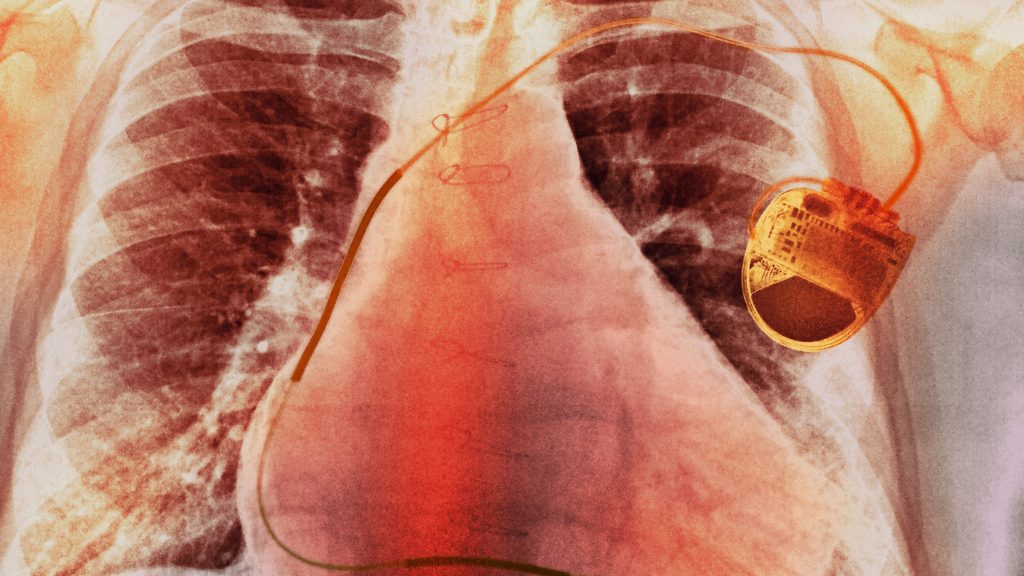

Egy kínai kutatócsoport áttörést ért el a szívritmus-szabályozás területén: olyan önellátó pacemakert fejlesztettek ki, amely a szív saját mozgásából termel elektromos energiát – írja a PCW. A Nature Biomedical Engineering magazinban bemutatott tanulmány szerint a hagyományos pacemakerek egyik legnagyobb problémáját oldja meg az eszköz, hiszen a jelenleg használt készülékek akkumulátorai nagyjából tíz évig biztosítanak energiát, ami ezen idő leteltével egy újabb, kockázatos és költséges műtéteket tesz szükségessé.

Az új eszköz a Kínai Tudományos Akadémia Egyeteme (UCAS), a Tsinghua Egyetem és a Pekingi Egyetem hét éves közös munkájának az eredménye. A pacemaker egy integrált energia-visszanyerő modult használ, amely a szívverés során keletkező mechanikai energiát elektromágneses indukcióval alakítja át árammá.

A kapszula méretű, vezeték nélküli pacemaker biokompatibilis anyagokból készült, és minimálisan invazív eljárással, a combvénán keresztül ültethető be. Teljesítménye átlagosan 120 mikrowatt, ami bőven meghaladja a stabil működéshez szükséges 10 mikrowattot. Egy egyhónapos állatkísérlet során egy súlyos szívritmuszavarral küzdő sertésben a készülék kizárólag a szív saját energiáját felhasználva tartotta fenn a normál ritmust.